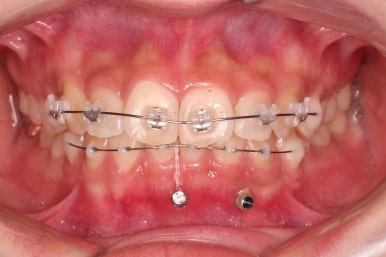

3. 치료경과

우선 윗니 앞니는 장치를 부착했고요.

아래 앞니는 장치 부착 이전에 아래로 앞니를 내려줄 미니스크류를 식립했습니다.

미니스크류가 단단하게 붙었을 시점에 아래 앞니도 장치를 부착하고요.

과개교합 개선을 위해서 미니스크류까지 힘을 줘서 아래 앞니를 내려줍니다.

이번 환자분이 사용한 장치는 엠파워 클리어라고 하는 자가결찰 세라믹 장치입니다.

일반적으로 클리피씨라고 많이 알고 계시는 장치가 "자가결찰 세라믹" 종류이며 여러 종류 중 엠파워 클리어도 있습니다.

제조사만 일본(클리피)이냐 미국(엠파워)이냐의 차이입니다.

아래 앞니는 브라켓보다는 훨씬 작은 미니튜브 장치를 사용했습니다.

과개교합의 경우 브라켓을 부착하게 되면 씹히게 되어 치료과정이 수월하지 못하기 때문이죠.

장치 부착 시점의 장치가 보이는 모습과 입매 변화 관찰해 주시고요.